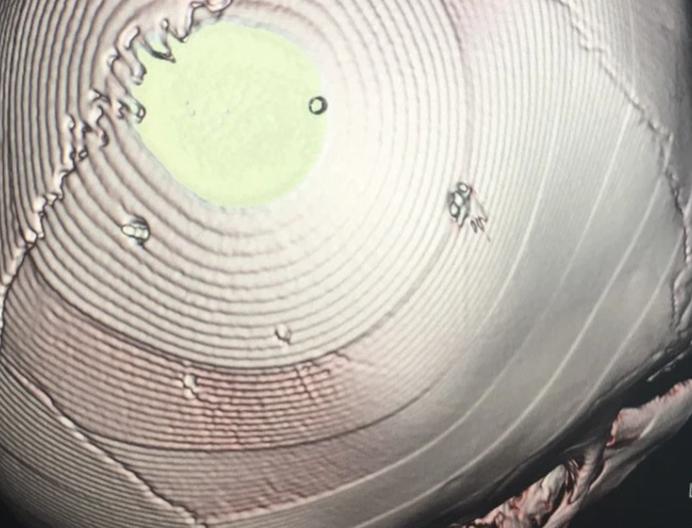

Sau khi tiến hành đặt ống, chụp phim, các bác sĩ phát hiện phim chụp có hình ảnh cản quang trên hộp sọ. Chẩn đoán sơ bộ xác định bệnh nhi hôn mê, nghi viêm màng não.

Tình trạng của em bé rất nặng, tỷ lệ tử vong cao nên được chuyển lên BV Xanh Pôn để điều trị. Bệnh viện đã tiến hành chụp cắt lớp, dựng hình phát hiện những hình ảnh giống như đinh ở sọ và tổ chức não của bé. Nghi bệnh nhi bi bạo hành, 2 BV đã báo cơ quan công an để xác minh.